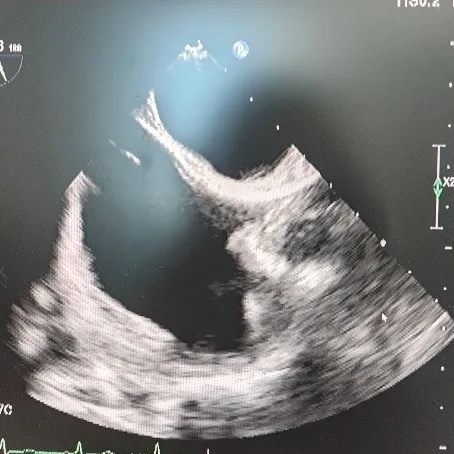

超声所见:经食管超声心动图+灰阶三维成像+彩色三维成像:卵圆孔未闭可吸收封堵器置入术后:未见残余分流,可吸收封堵器位置回声与心肌组织回声接近。

超声结论:未见残余分流。